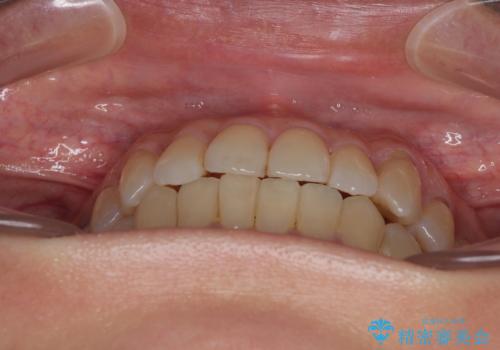

受け口と八重歯を改善 インビザライン矯正治療

- 前歯のデコボコや八重歯を治したいとのことで来院された患者様です。

受け口傾向の骨格であり、前歯はクロスバイトまたは切端咬合となっており、下顎を中心に歯列全体の後方移動を行い、IPR(歯と歯の間を削る)によってデコボコが解消するように設計し、インビザラインにより治療を行うこととしました。

受け口傾向のインビザライン矯正は比較的治療を行いやすいため、きれいに仕上げることができました。舌の突出癖が顕著であったため、改善のためのトレーニングをしっかりと行っていただきました。